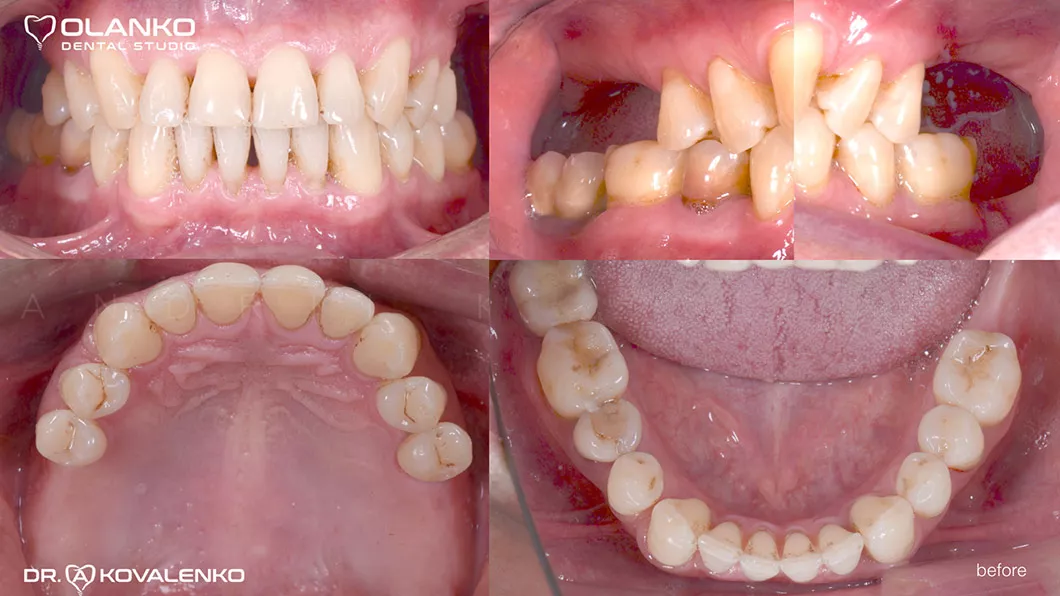

Пацієнт звернувся зі скаргами на відсутність жувальної групи зубів.

Лікування: операція кісткової пластики на верхній щелепі (двосторонній синус-ліфтинг). Установка 4-х зубних імплантатів на верхній щелепі і один зубний імплантат на нижній щелепі. Пластика м'яких тканин в області імплантатів.

Ситуація до